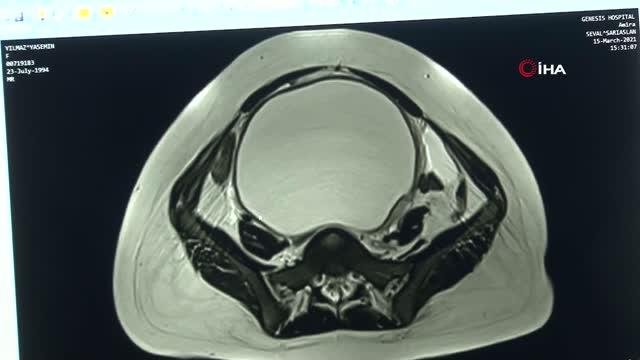

Yumurtalık kistlerinin sanılanın bilakis birçok bayan tarafından fark edilmediğini belirten Doç. Dr. Lebriz Hale Aktün, "Çoğu zararsız ve zaten ...

Yumurtalık kistlerinin sanılanın tersine birden fazla bayan tarafından fark edilmediğini belirten Doç. Dr. Lebriz Hale Aktün, "Çoğu zararsız ve ...